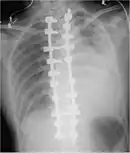

Thoracostomy

A tube thoracostomy unit

Blood in the cavity can be removed by inserting a drain (chest tube) in a procedure called a tube thoracostomy. This procedure is indicated for most causes of hemothorax, but should be avoided in aortic rupture which should be managed with immediate surgery.[30] The thoracostomy tube is usually placed between the ribs in the sixth or seventh intercostal space at the mid-axillary line.[15] It is important to avoid a chest tube becoming obstructed by clotted blood as obstruction prevents adequate drainage of the pleural space. Clotting occurs as the clotting cascade is activated when the blood leaves the blood vessels and comes into contact with the pleural surface, injured lung or chest wall, or the thoracostomy tube. Inadequate drainage may lead to a retained hemothorax, increasing the risk of infection within the pleural space (empyema) or the formation of scar tissue (fibrothorax).[31] Thoracostomy tubes with a diameter of 24–36 F (large-bore tubes) should be used, as these reduce the risk of blood clots obstructing the tube. Manual manipulation of chest tubes (referred to as milking, stripping, or tapping) is commonly performed to maintain an open tube, but no conclusive evidence has demonstrated that this improves drainage.[8] If a chest tube does become obstructed, the tube can be cleared using open or closed techniques.[32] Tubes should be removed as soon as drainage has stopped, as prolonged tube placement increases the risk of empyema.[33][6]